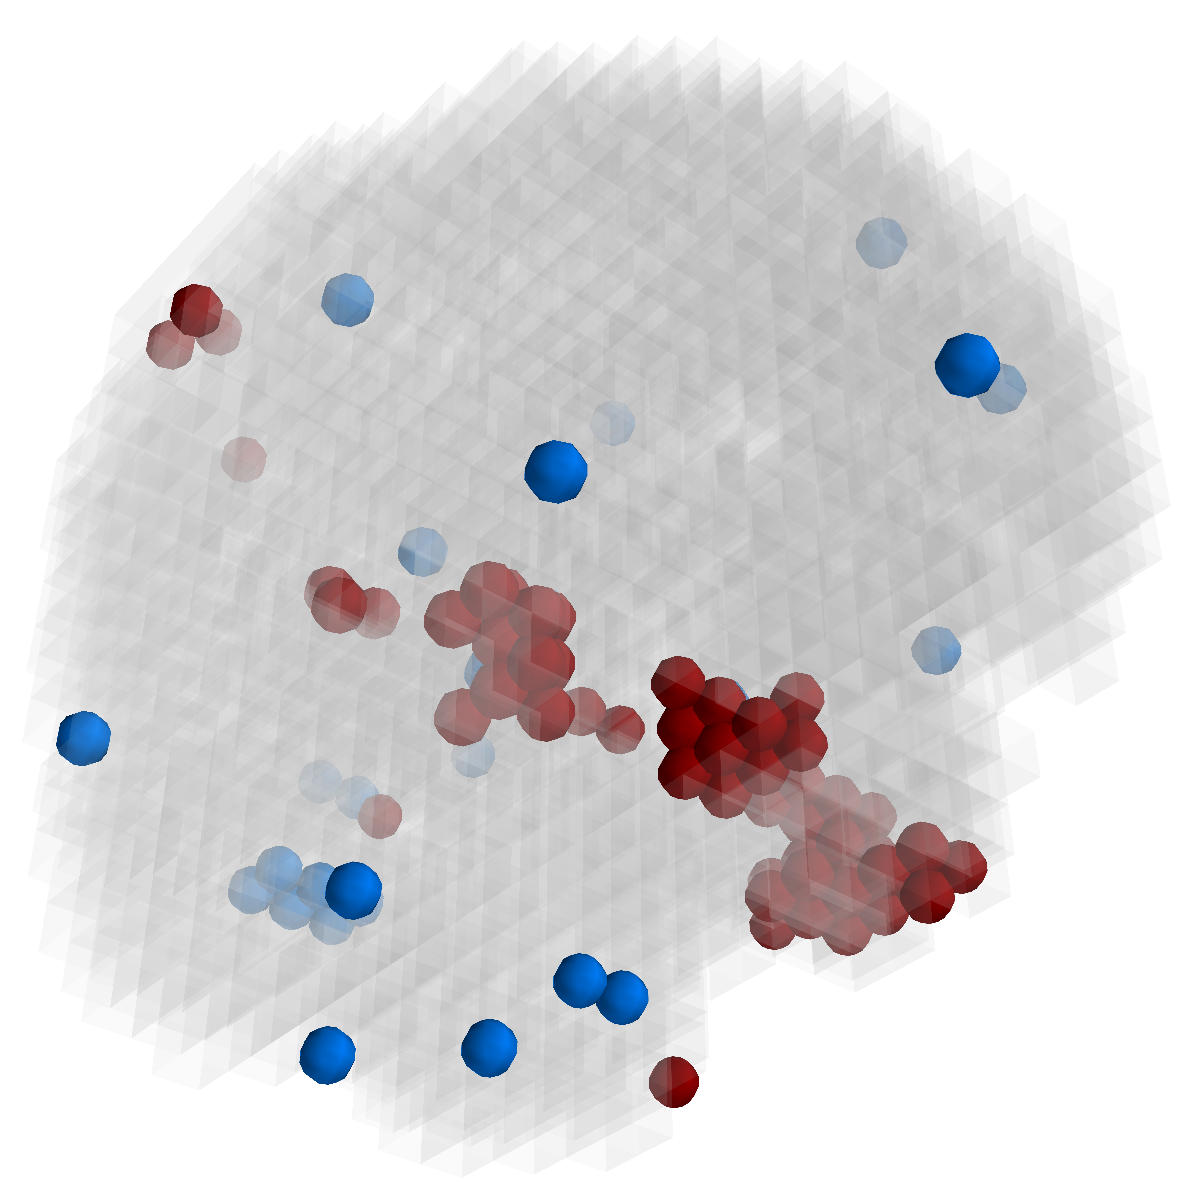

Figure 3: Stability of selected voxels across different folds of the cross-validation. The results of 5 different folds are shown in (a)-(e). The voxels with positive β𝛽\beta are in brown, negative ones are in blue. The common/overlapped voxels selected in all 10 folds are shown in green (f). The top row illustrates voxels selected by the lasso model, the mid row illustrates those of GFL and the bottom row shows those of n2superscript𝑛2n^{2}GFL.

Feature Stability. In Figure 3, we show the selected voxels across different folds of CV333Here, parameters were determined by accuracy. Similar results were observed using parameters producing same level of sparsity.. As shown, the selected voxels by lasso vary much across different folds, whereas the selected voxels by GFL are more stable. However, by assuming the positive correlation between the features and the disease labels in n2superscript𝑛2n^{2}GFL, we further increase the stability. To quantitatively evaluate the stability gain, we denote the variables of the k𝑘kth fold of CV as 𝜷(k)𝜷𝑘\boldsymbol{\beta}(k). We introduce two measurements here. In (?), the Estimation Stability (ES) is proposed to measure the stability of the estimation

where ##\# is the number of elements in a set. In Tab. 3, both measurements quantitatively suggest n2superscript𝑛2n^{2}GFL obtains much more stable voxels due to the consideration of the correlation between the features and the disease labels 444We notice that, in (?), the stability is computed using the top 50 positive voxels because these voxels are believe to be the most atrophied ones. By computing the stability of all non-zero voxels, the mDC of GFL drops around 30%percent3030\%. This clearly shows that the instability is caused largely by the undesirable voxels that disagree with the correlation prior (those scattered blue voxels in the mid row)..